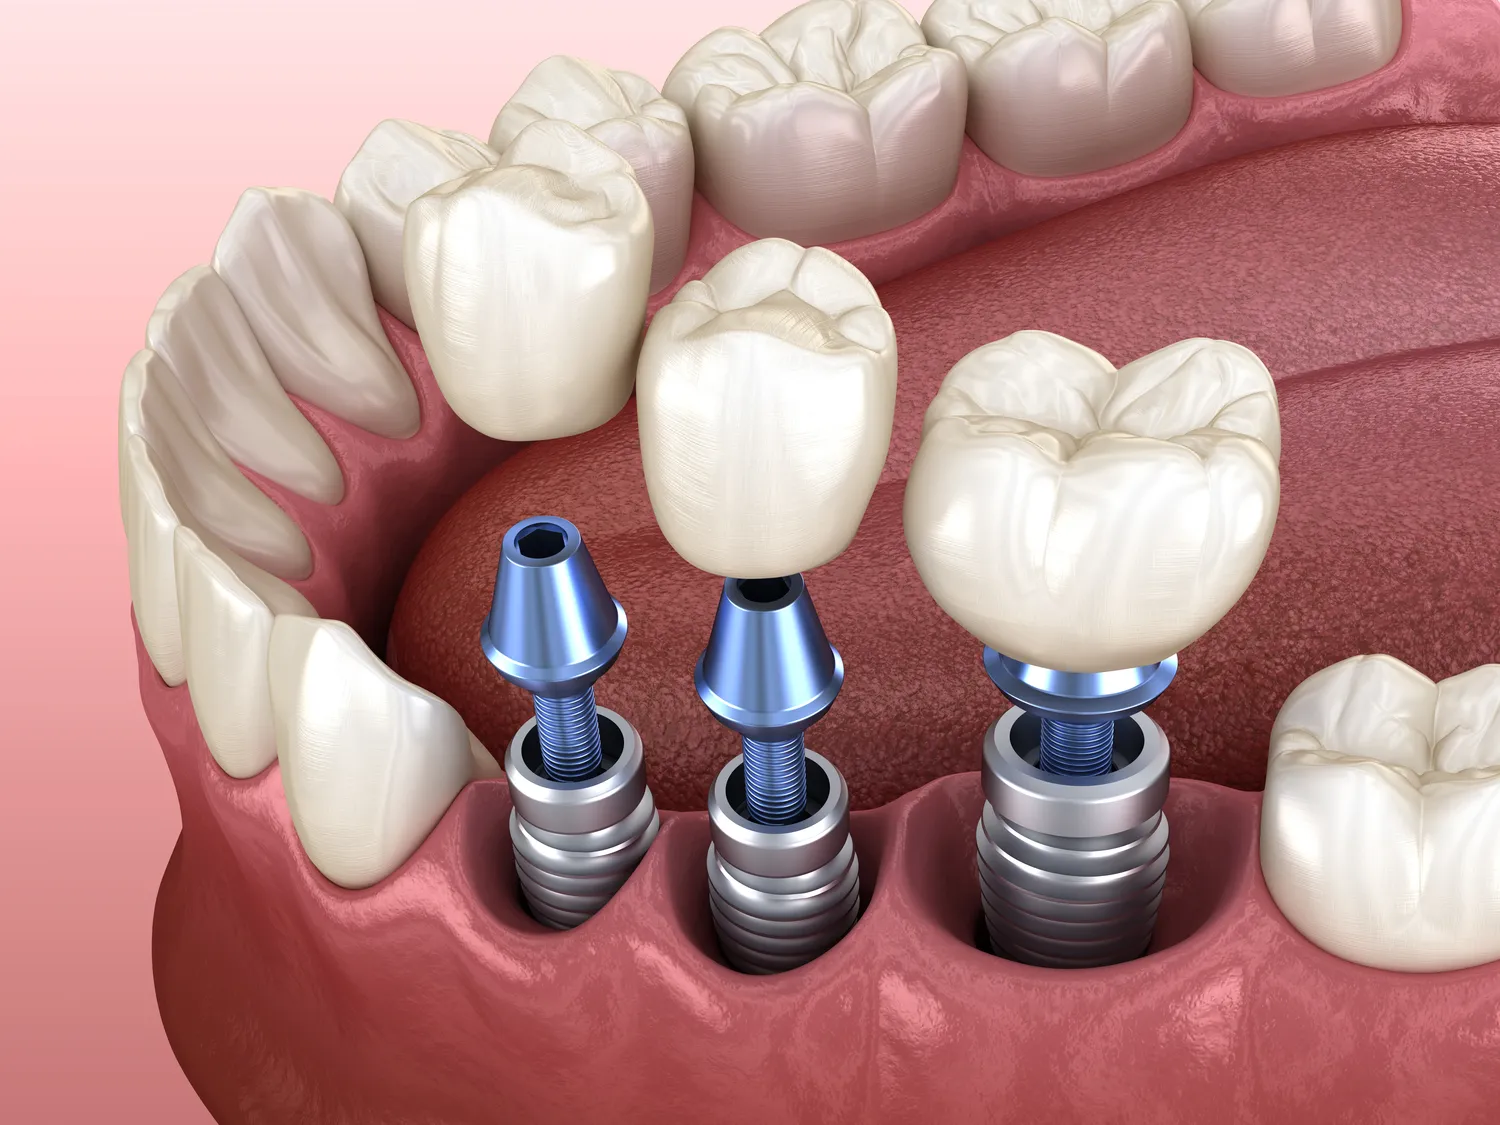

W ostatnich latach rozwój technologii w dziedzinie implantologii stomatologicznej przyczynił się do znacznego zwiększenia skuteczności oraz bezpieczeństwa zabiegów wszczepiania implantów. Jednym z najważniejszych osiągnięć jest zastosowanie cyfrowych technologii obrazowania, takich jak tomografia komputerowa, która pozwala na dokładne zaplanowanie zabiegu oraz precyzyjne umiejscowienie implantu w kości. Dzięki temu lekarze mogą uniknąć potencjalnych komplikacji i lepiej dostosować procedurę do indywidualnych potrzeb pacjenta. Kolejnym innowacyjnym rozwiązaniem są implanty o zmodyfikowanej powierzchni, które sprzyjają szybszemu gojeniu się tkanek i lepszemu zintegrowaniu implantu z kością. Współczesne materiały wykorzystywane do produkcji implantów są coraz bardziej biokompatybilne, co oznacza, że organizm lepiej je toleruje, a ryzyko odrzutu jest minimalizowane. Dodatkowo, techniki takie jak druk 3D umożliwiają tworzenie spersonalizowanych implantów, które idealnie pasują do anatomicznych warunków pacjenta.

Proces gojenia po wszczepieniu implantu zębowego jest kluczowym etapem całej procedury i może trwać od kilku tygodni do kilku miesięcy, w zależności od indywidualnych warunków pacjenta oraz rodzaju zastosowanego implantu. Po zabiegu pacjent może odczuwać pewien dyskomfort lub ból w okolicy wszczepienia; lekarz zazwyczaj przepisuje leki przeciwbólowe oraz antybiotyki w celu zapobiegania infekcjom. W pierwszych dniach po zabiegu zaleca się unikanie twardych pokarmów oraz dbanie o higienę jamy ustnej poprzez delikatne szczotkowanie okolic wokół implantu. Kluczowym elementem procesu gojenia jest integracja implantu z kością szczęki; ten proces nazywa się osteointegracją i jest niezbędny dla stabilności implantu. W tym czasie ważne jest regularne kontrolowanie stanu zdrowia jamy ustnej u dentysty, który oceni postęp gojenia oraz ewentualnie zaleci dodatkowe działania terapeutyczne.

Czas trwania całego procesu leczenia implantologicznego może być różny w zależności od wielu czynników, takich jak stan zdrowia pacjenta, ilość brakujących zębów czy potrzeba przeprowadzenia dodatkowych zabiegów przygotowawczych. Zazwyczaj cały proces można podzielić na kilka etapów: konsultację przedzabiegową, sam zabieg wszczepienia implantu oraz okres gojenia się tkanek przed wykonaniem korony protetycznej. Konsultacja zazwyczaj zajmuje jedną wizytę u dentysty i obejmuje dokładną ocenę stanu zdrowia jamy ustnej oraz planowanie leczenia. Sam zabieg wszczepienia implantu trwa zazwyczaj od 1 do 2 godzin w zależności od liczby implantów oraz skomplikowania przypadku. Po wszczepieniu następuje okres gojenia się tkanek; w przypadku standardowych implantów trwa on zazwyczaj od 3 do 6 miesięcy, podczas gdy u pacjentów wymagających dodatkowych zabiegów (np. odbudowy kości) czas ten może być dłuższy.